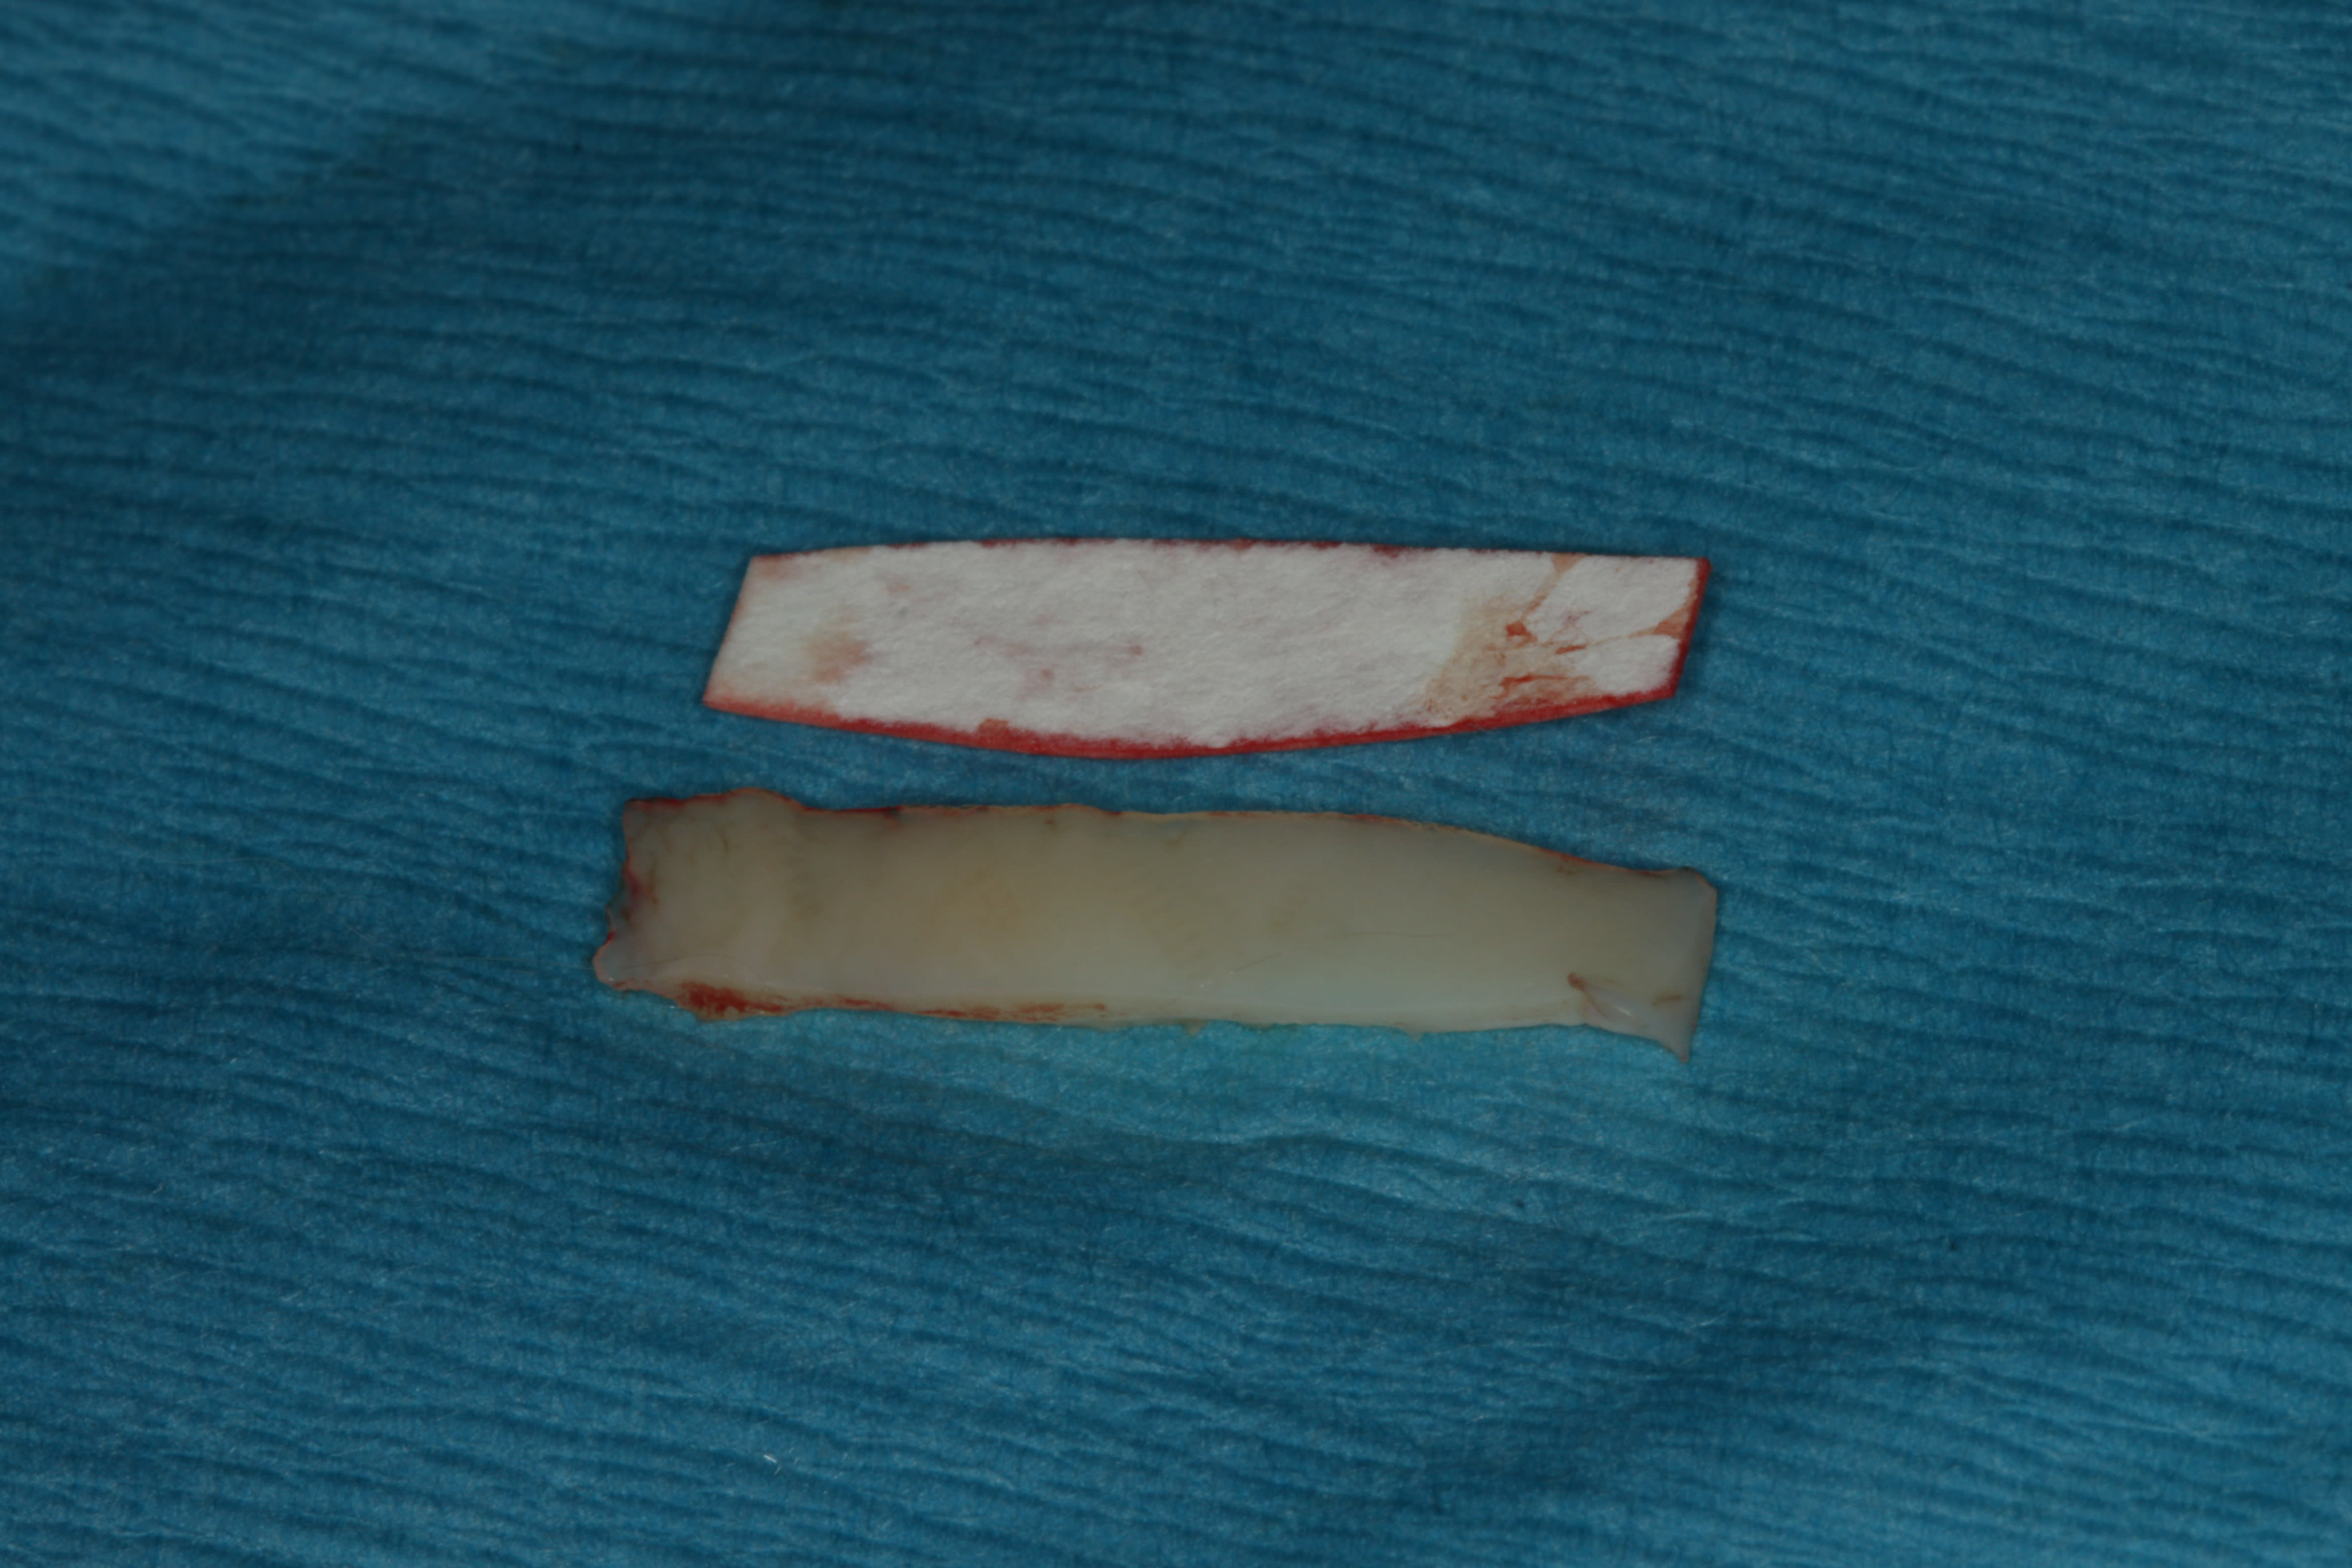

C'est magnifique et c'est élégant. Tu devrais photographier le moment où tu joues au maitre sushi avec ton scalpel pour enlever l'épithelium.

Palais, zone 24-26